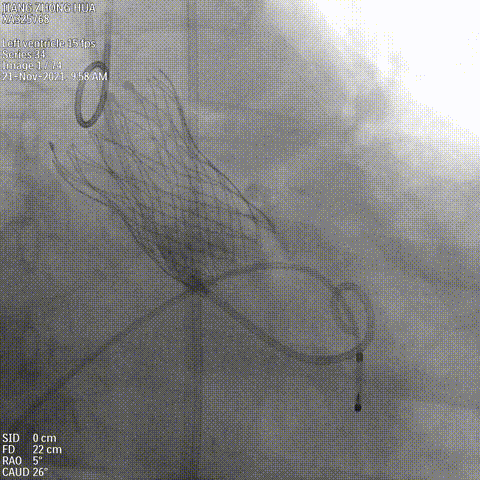

瓣膜释放

术后造影

术后即刻评估

术后压差从110 mmHg降至3 mmHg无瓣周漏,瓣膜正常工作,血流动力学即刻得到改善。